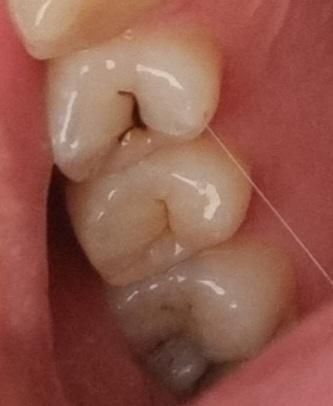

내일 치과 방문 예정인데 미리 생각을 해두고 싶어서요. 위의 사진이 약 1년 반 전의 치아 상태, 아래가 방금 찍은 사진입니다 위에서 3번째 이는 신경치료하기로 했고, 나머지 두 개는 지켜보고 아프면 충치치료 하자고 하셨는데... 사진 비교했을 때 진행이 많이 된 편일까요

진행이 많이 된것처럼 보이지 않지만 해당 정도의 충치라면 치료를 하는 것이 맞아 보입니다. 충치가 상당히 진행되었을 가능성이 매우 높아 보입니다. 다만 정확히 진행 정도를 알기 위해서는 x-ray 등의 촬영이 필요합니다. 따라서 가까운 치과 방문 후 x-ray 촬영을 권해드립니다.

진행이 되고 있는 것으로 보입니다. 치아를 직접 검사해봐야겠으나 치료가 필요해보입니다.

어금니쪽 충치는 많이 진행된거 같습니다 육안상으로는 판단하기가 어렵고 치과에 가셔서 엑스레이를 찍어봐야 정확히 알수 잇을것같습니다.

사진으로는 정확한 확인이 어려워 보입니다. 충치가 전반적으로 진행이 되고 있는 것으로 보입니다. 충치가 진행되고 있다면 빠르게 치료를 하는 것이 더 좋을 수 있습니다.

사진으로만 보기에는 정지우식으로 보이고 맨 위

치아는 침착물이 조금 많아서 긁어내고 방사선 사진을 찍어봐야 정확하게 알 수 있을 것 같습니다만 평소에 통증이 없었다면 크게 문제가 없을 것으로 보입니다.

셋다 충치는 진행중인 것으로 보입니다 이정도면 정지충치의 상태는 아니기 때문에 충치치료, 신경치료 늦지 않게 진행하는 것을 추천드립니다